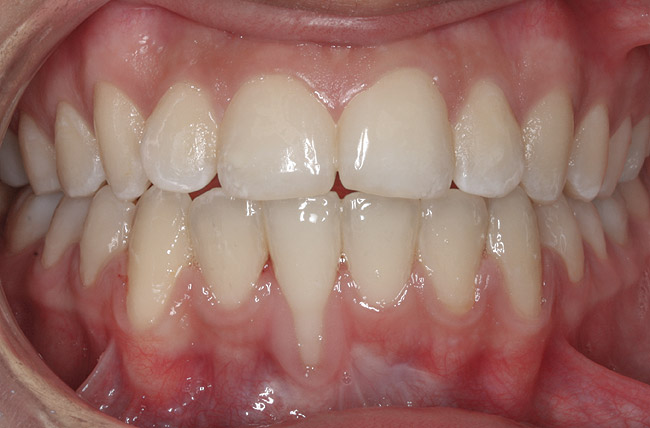

CASE 4 Fig 9. Post-orthodontic Miller Class II recession treated with surgical coverage only in spite of the incorrect inclination of the affected tooth. Clinical view immediately post-orthodontic treatment.

Figure 9

Fig 10. Same patient 5 months later showing worsening of the recession.

Figure 10

Fig 11. Same patient 1 year after connective tissue graft, showing partial root coverage.

Figure 11